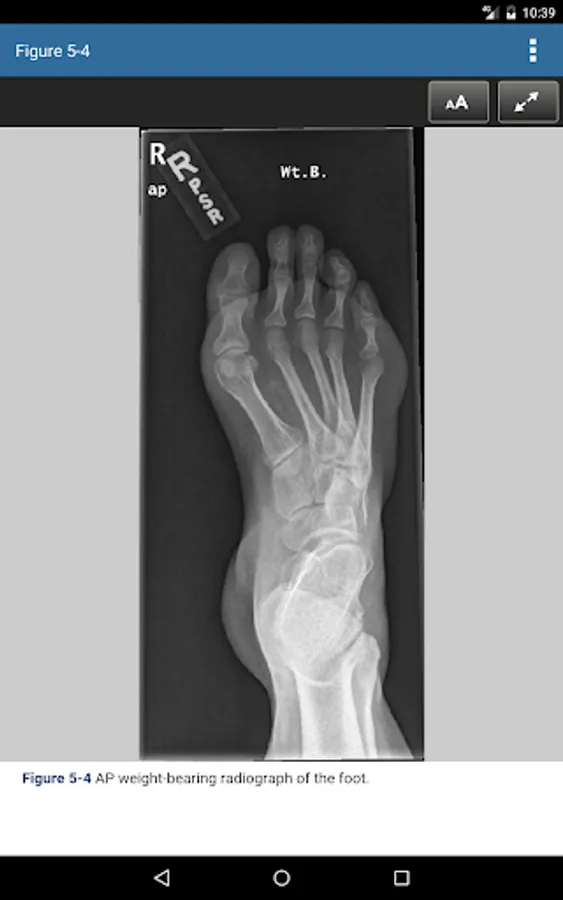

• Color photographs and illustrations to complement the text